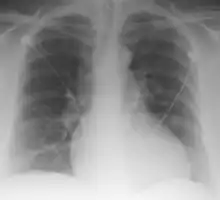

Palla's sign is a clinical sign in which an enlarged right descending pulmonary artery is seen on the chest x-ray in patients with pulmonary embolism. It is of low sensitivity, and its specificity is not known. It exhibits as a "sausage" appearance on X-ray. [1] It is named after italian radiologist Antonio Palla. In 1983, he published his observations that close to 25% of patients with pulmonary embolism had a chest x-ray sign of enlarged right descending pulmonary artery.[2][3]